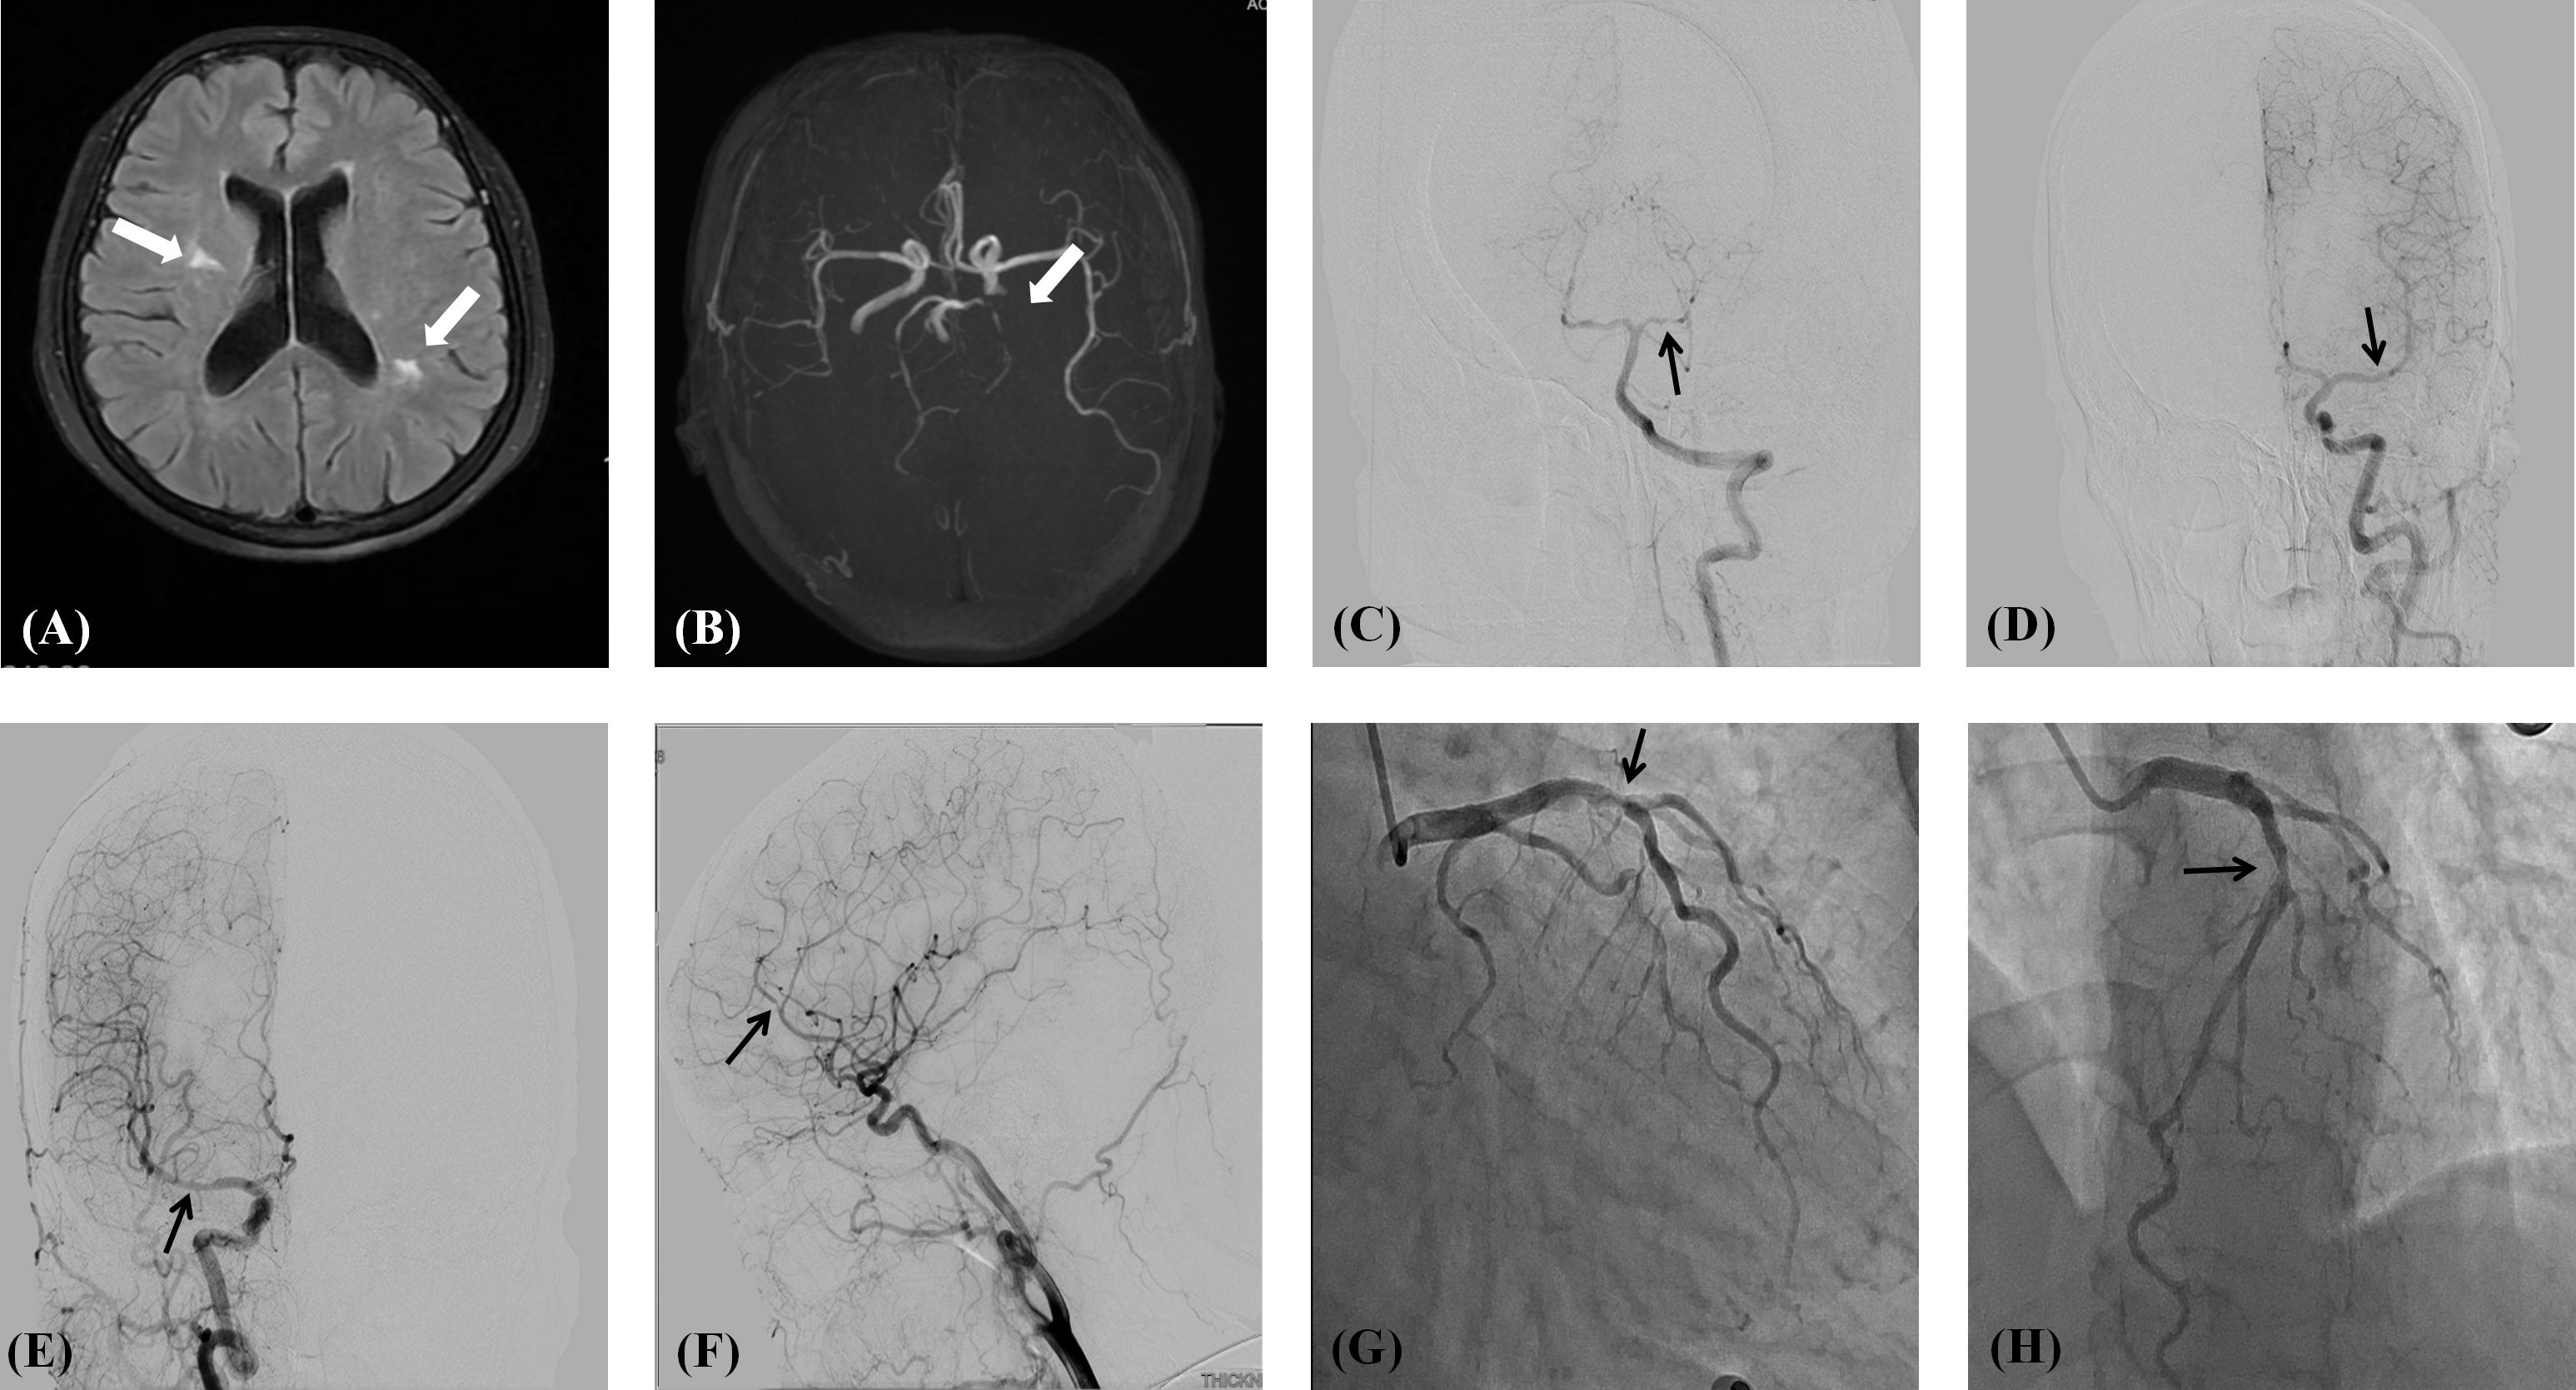

Introduction: Primary Sjögren's syndrome (pSS) is a heterogeneous autoimmune disorder that may be associated with systemic manifestations such as pulmonary or articular involvement.Compared to other autoimmune diseases, vascular injury and accelerated atherosclerosis in pSS are less studied. Case presentation: A 51-year-old woman presented with a 2-month history of dizziness, chest tightness, and exertional dyspnea. Vascular imaging revealed multifocal stenoses in the left anterior descending coronary artery (70%), bilateral middle cerebral arteries, right anterior cerebral artery, and left posterior cerebral artery. Her only traditional cardiovascular risk factor was hypertension, and she reported only mild xerostomia. Serology showed anti-SSA positivity. Schirmer's test was abnormal, and a labial gland biopsy confirmed focal lymphocytic sialadenitis (≥1 foci/4 mm²), leading to a pSS diagnosis per 2016 ACR-EULAR criteria. She responded favorably to a combination of immunomodulators (hydroxychloroquine and total glucosides of paeony), antiplatelet therapy, and statins, with symptom resolution at follow-up. Conclusion: This case represents an exceptionally rare documented instance of pSS simultaneously affecting both cerebral and coronary arterial systems. It underscores that severe multifocal arterial stenosis can present as the initial manifestation of this disease, even in the absence of prominent dryness symptoms. This highlights the necessity for vascular assessment in pSS patients and the urgency of conducting autoimmune evaluations in cases of unexplained multivessel arteriopathy.